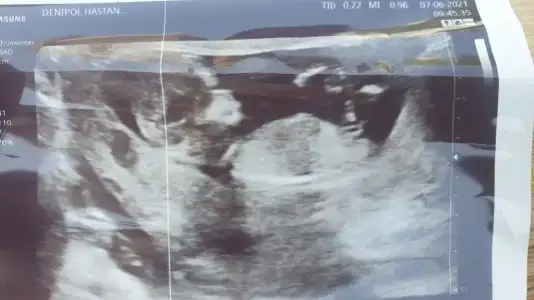

Teyzoşları bize de tahmin yapar mısınız doktorumuz yoğun ısrarımızla bacak arasına bakıp bi tahmin yürüttü ama sakın alışveriş felan yapma değişebilir diye tembihledi beni yine de merak ediyorum 😇